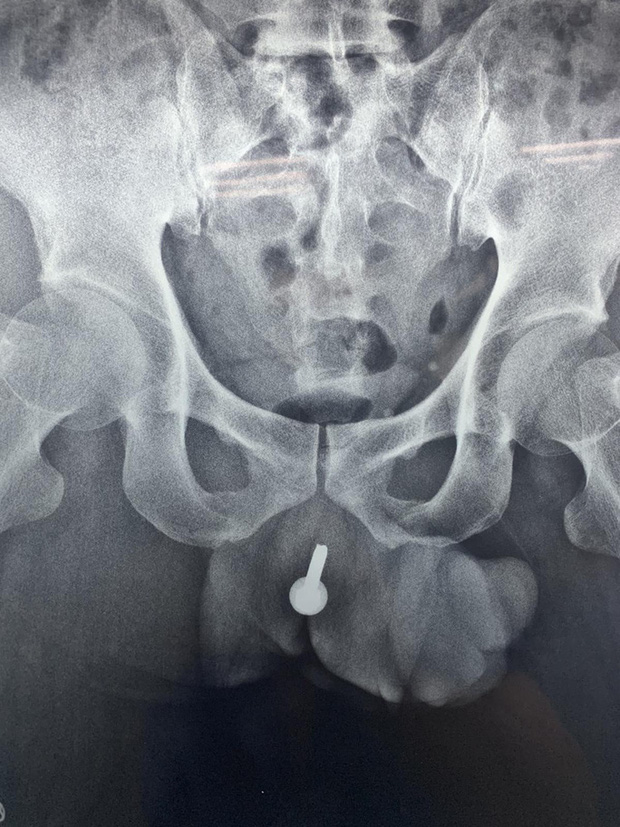

20/01/2021 00:48Người đàn ông đến bệnh viện với chiếc ốc vít dài 6cm xoáy vào giữa dương vật

Bệnh nhân là ông N.V.T (45 tuổi, ở An Giang) nhập việc cấp cứu trong tình trạng đau đớn vùng sinh dục và bí tiểu, có dấu hiệu nhiễm trùng.

Qua kiểm tra, các bác sĩ phát hiện một dị vật dài khoảng 6 cm nằm dọc theo niệu đạo. Ngay lập tức, ông T. được mổ cấp cứu dẫn lưu nước tiểu ra da, tránh nguy cơ nhiễm khuẩn, đồng thời phẫu thuật khẩn lấy dị vật là chiếc ốc vít dùng trong xây dựng.

Ông T. cho hay do quá say rượu nên ông bị một bạn nhậu đùa giỡn nhét ốc vít vào dương vật chỉ còn đầu vít lồi bên ngoài.

Theo ThS-BS Đỗ Lệnh Hùng, Trưởng Đơn vị Niệu đạo Bệnh viện Bình Dân, nơi đây từng tiếp nhận các trường hợp nhét đinh tán, ốc vít, búi dây cước, tăm… vào niệu đạo. Nếu không được can thiệp kịp thời, dị vật sẽ gây viêm, nhiễm khuẩn, diễn tiến hẹp niệu đạo, áp xe vùng sinh dục rất nguy hiểm.